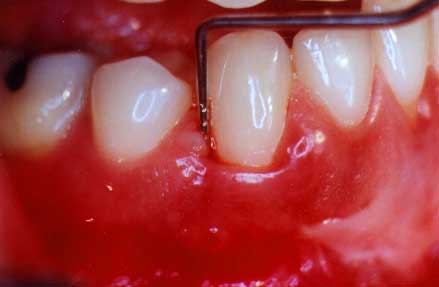

periodontal probe in pocket

Probe in the Pocket

This print shows the probe in the pocket to a depth of 8 mm.

periodontal probe outside pocket

Probe Outside of the Pocket

You can see how deep the probe did actually go into this disease pocket. This is approximately 8 millimeters and shows how much gum and bone destruction has occurred